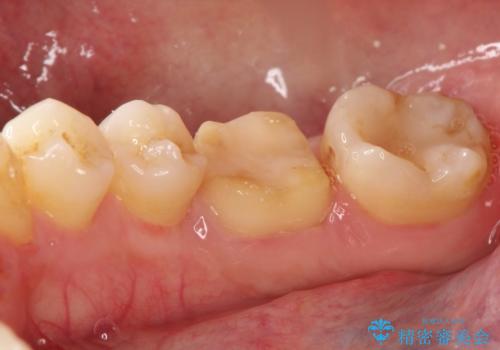

- 以前治療した右下の奥歯の歯の中が虫歯になっている気がするとのことで来院されました。

レントゲン上と視診上では確認できなかったのですが、患者様の希望もあり、一度かぶせ物を外して内部を確認し、オールセラミックを再度装着する計画としました。

やはり内部では少量の虫歯がありましたので、拡大鏡使用して虫歯を除去しました。

虫歯の取り残した場合は将来的に再治療が高い確率で必要となります。

今回精度の高い治療を行うことで、再治療の可能性を限りになく小さくできました。